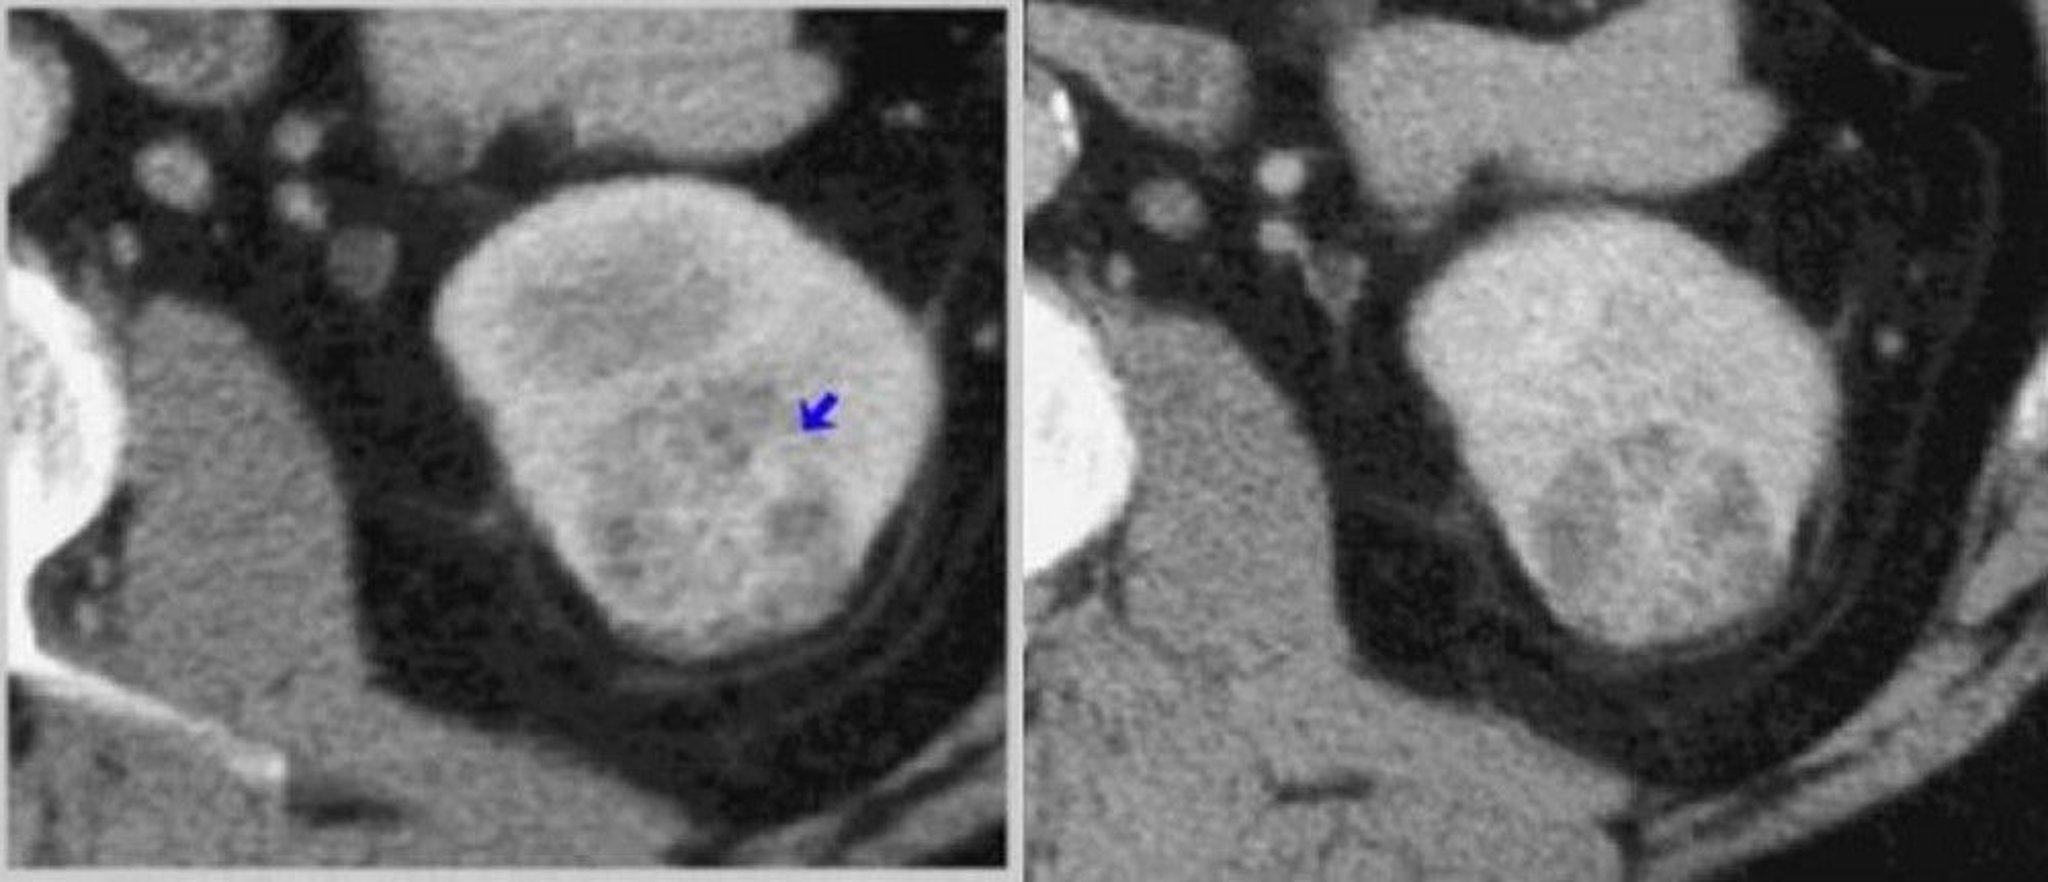

КТ-скан почки с контрастным усилением (кортикомедуллярная и нефрогенная фазы)

Слева на КТ-скане кортикомедуллярной фазы показана опухоль с гетерогенным усилением (стрелка). Справа – КТ-скан нефрографической фазы, которая позволяет лучше определить опухоль.